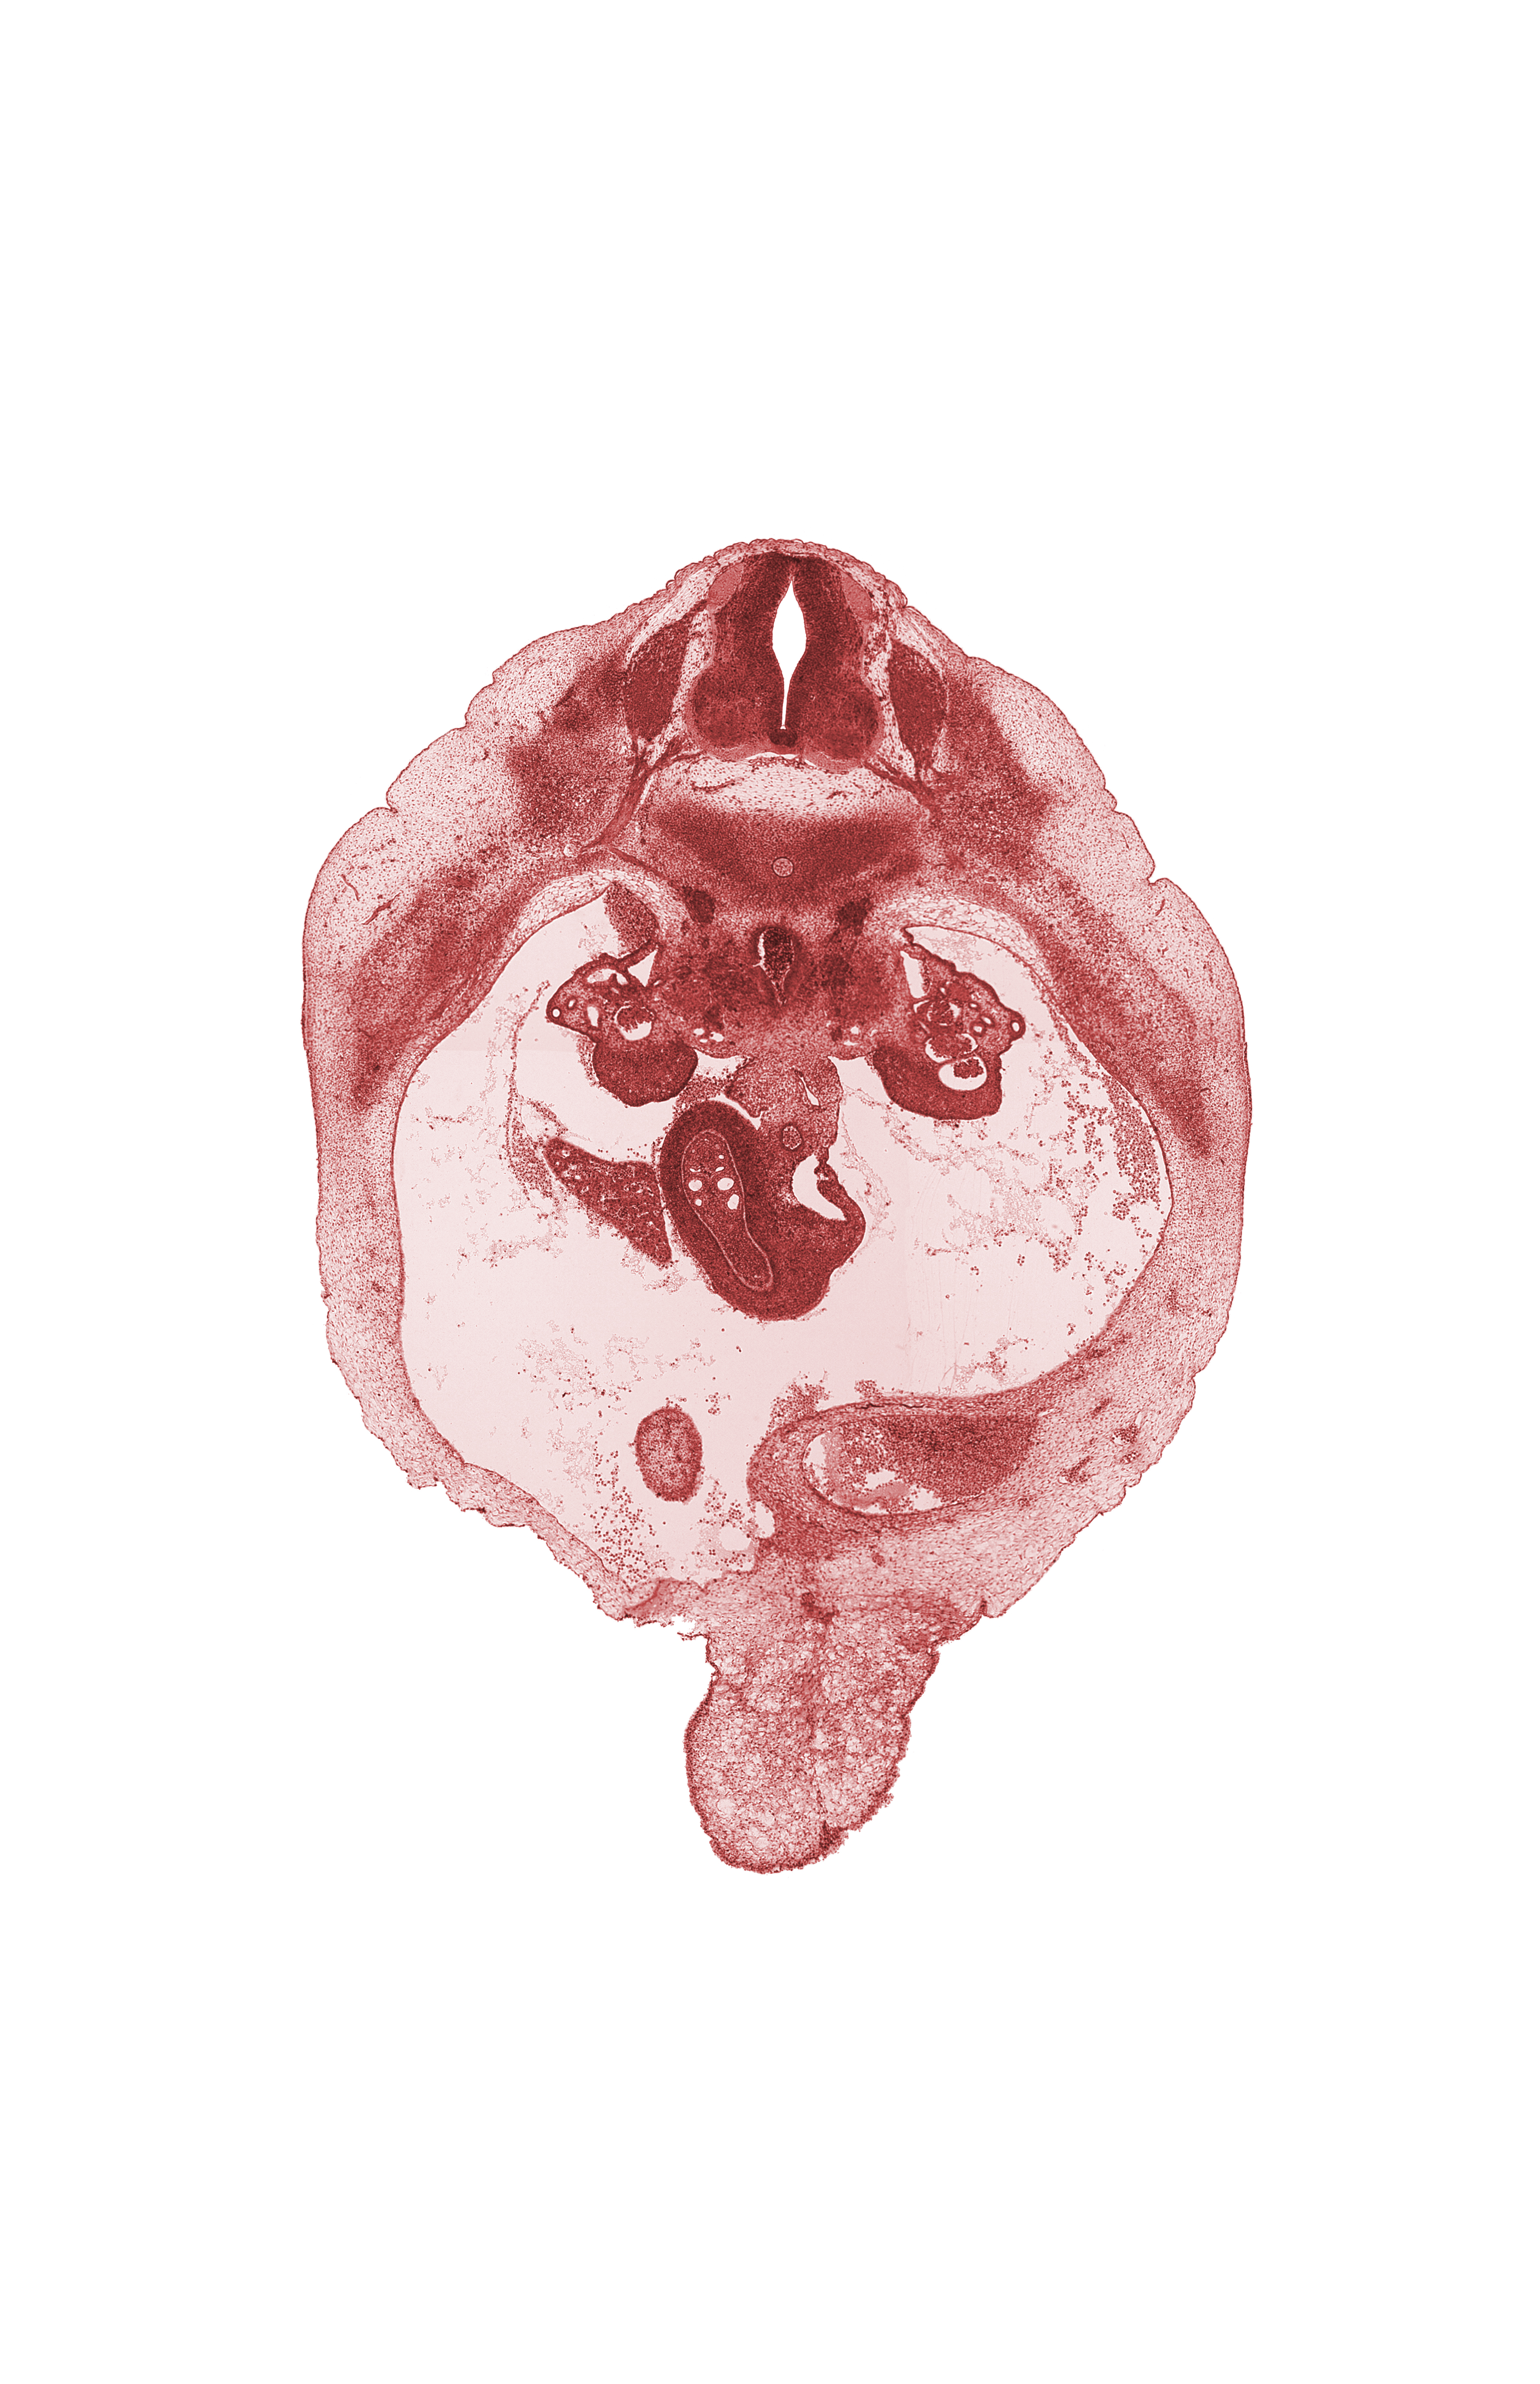

Carnegie Embryo #6520 | Location: 21-04-01

Keywords: T-10 spinal ganglion, aorta, duodenum, edge of gall bladder, intermediate zone, junction of bile duct and duodenum, marginal zone, mesonephric duct, paramesonephric groove, peritoneal cavity, right lobe of liver, superior mesenteric artery, superior mesenteric vein, umbilical vein, ventricular zone

Source: The Virtual Human Embryo.